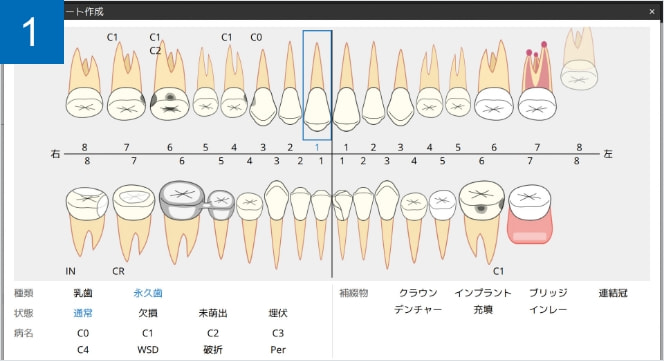

デンタルチャート作成

歯牙の種類や病状、補綴物などの口腔内の情報を登録する事ができます。

カリエスや補綴物は、近心遠心、唇側(頬側)、舌側(口蓋側)の指定も可能です。